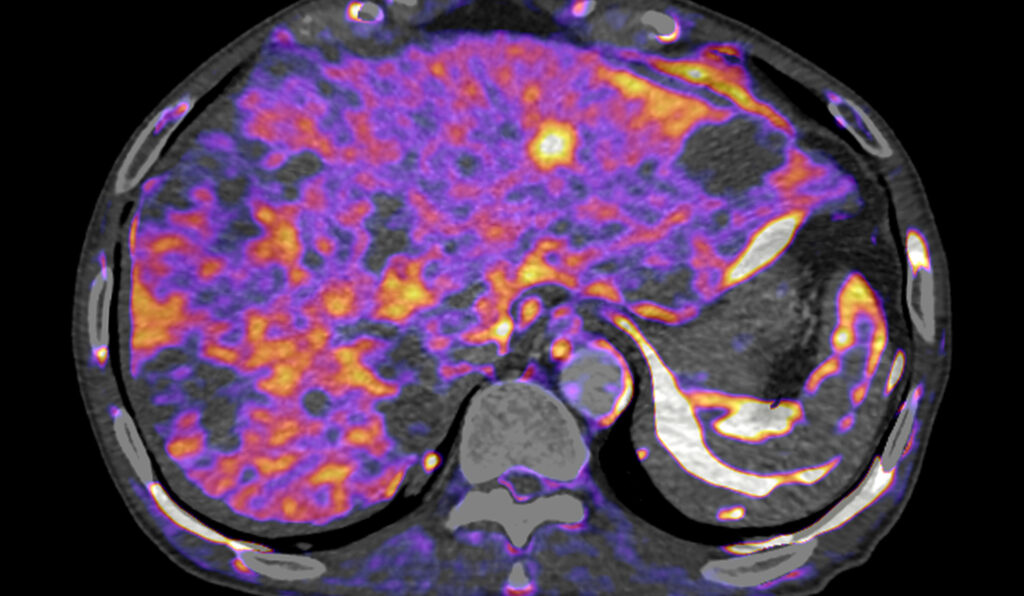

Cardiovascular

A full suite of advanced imaging workflows for CT, MR, XA, UL and PET/SPECT to facilitate assessment, diagnosis and treatment of diseases related to the heart and vessels.